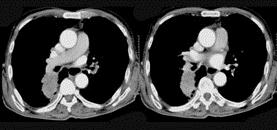

问题 72岁,男,呼吸急促、气喘4个月,请结合胸片和CT,选出最可能的诊断 ( )

选项 A、韦格肉芽肿 B、支气管腺瘤 C、错构瘤 D、肺结核 E、肺癌

答案 E